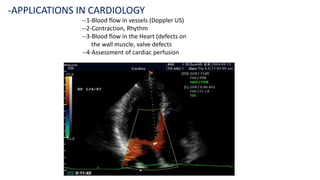

-APPLICATIONS IN CARDIOLOGY

--1-Blood flow in vessels (Doppler US)

--2-Contraction, Rhythm

--3-Blood flow in the Heart (defects on

the wall muscle, valve defects

--4-Assessment of cardiac perfusion